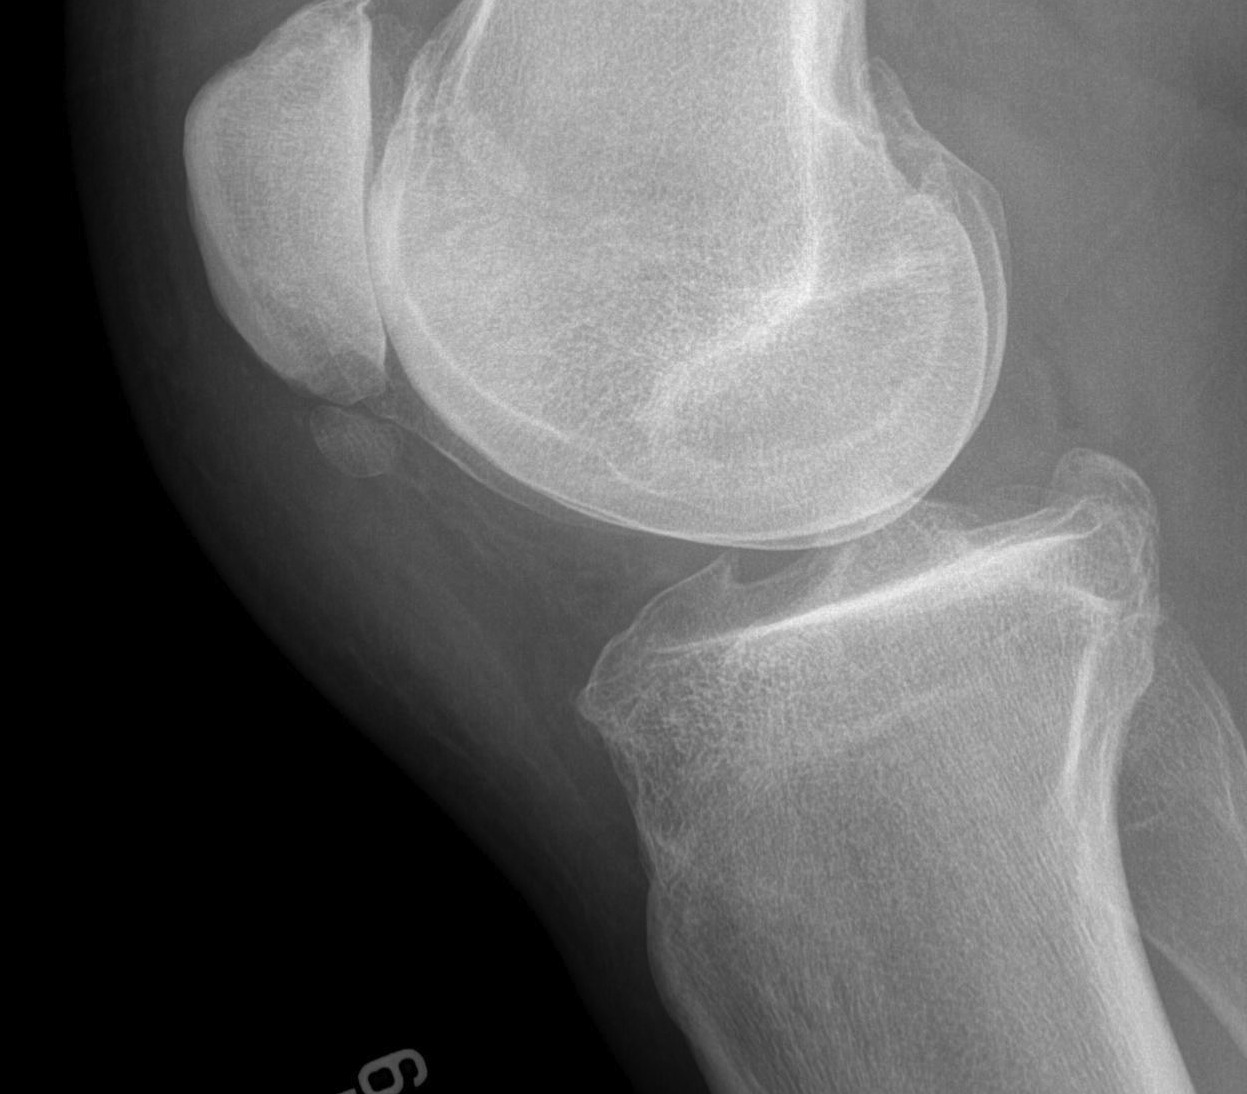

X-ray

Usually normal

May see

- traction spurs

- calcification of patella tendon